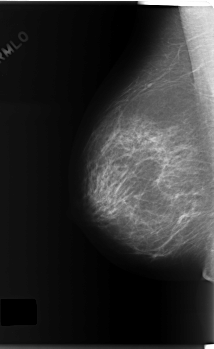

C_0165_1.RIGHT_MLO

RIGHT_MLO LINES 5920 PIXELS_PER_LINE 3632 BITS_PER_PIXEL 12 RESOLUTION 50 NON_OVERLAY